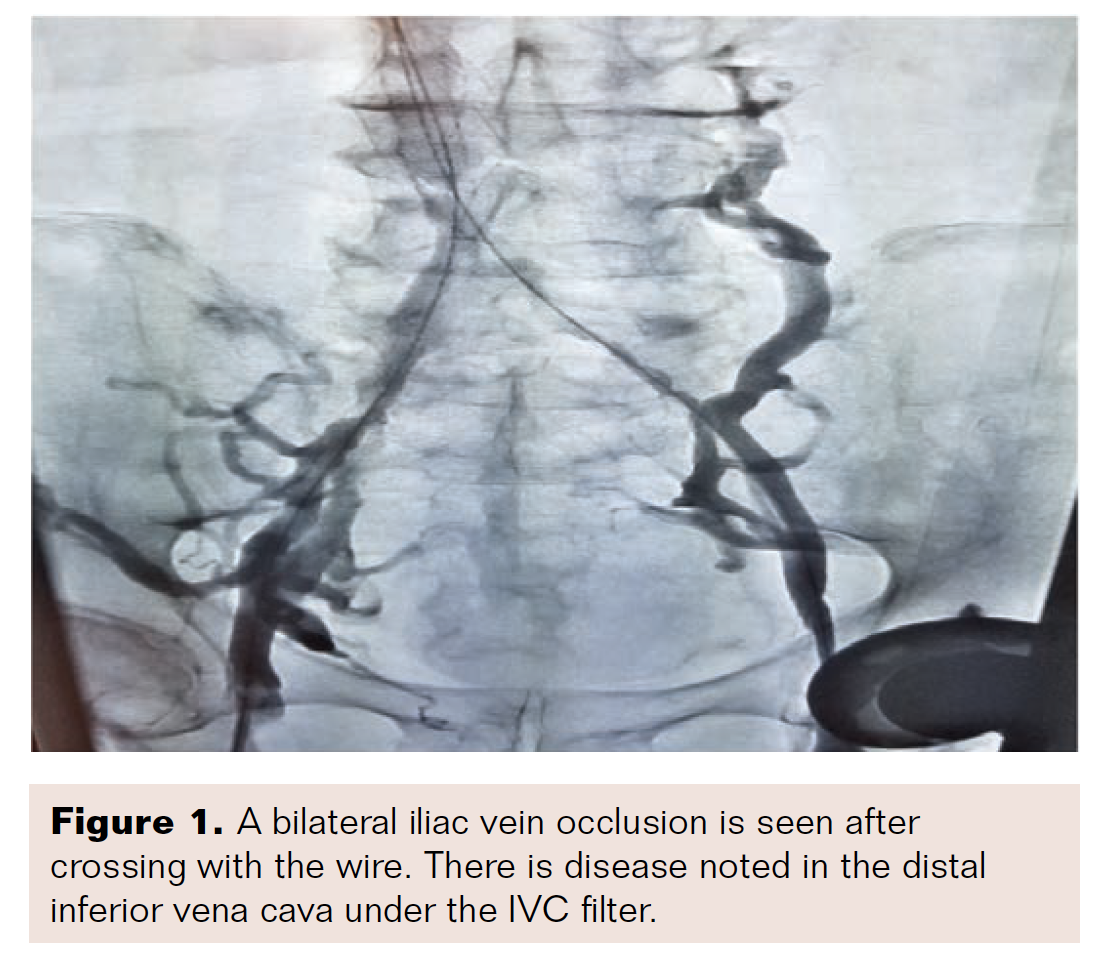

The CTO could not be crossed with a .035-inch Glidewire (Terumo). A stiff .014-inch guidewire and a 5 French support catheter were required for crossing. The first recorded images were obtained after the CTO had been crossed with the 5 French support catheter (Figure 1). After crossing, J-tipped .035-inch wires were placed in the IVC from the bilateral groins. We thought there was a post-thrombotic occlusion, so we performed rheolytic thrombectomy with the AngioJet ZelanteDVT thrombectomy catheter (Boston Scientific) in the bilateral iliac veins and into the IVC filter, after which intravascular ultrasound (IVUS) was performed (Figure 2).